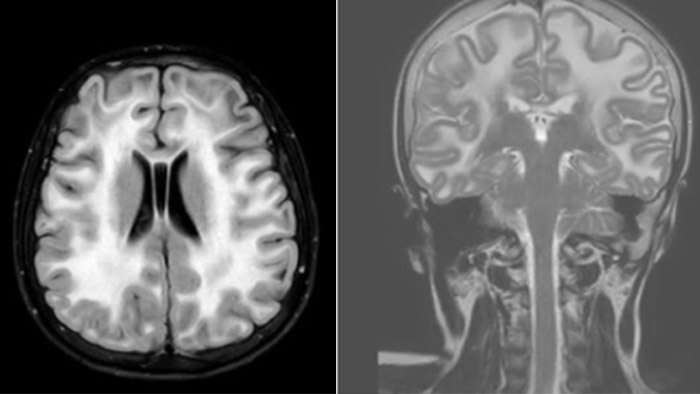

Leukodystrophy in a teenager

Rostral meningitis and arachnoiditis Both images are from the same 3D T1-weighted post contrast sequence in a newborn, under treatment.